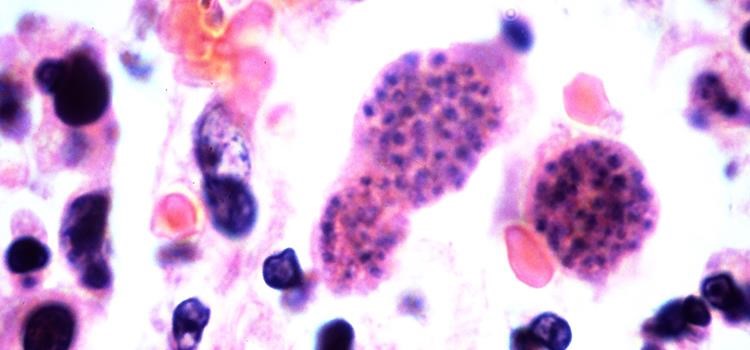

Top image: Toxoplasmosis is a disease that was introduced to Australia by cats and affects Australian mammals.  Photo: Yale Rosen Flickr CC BY-SA 2.0